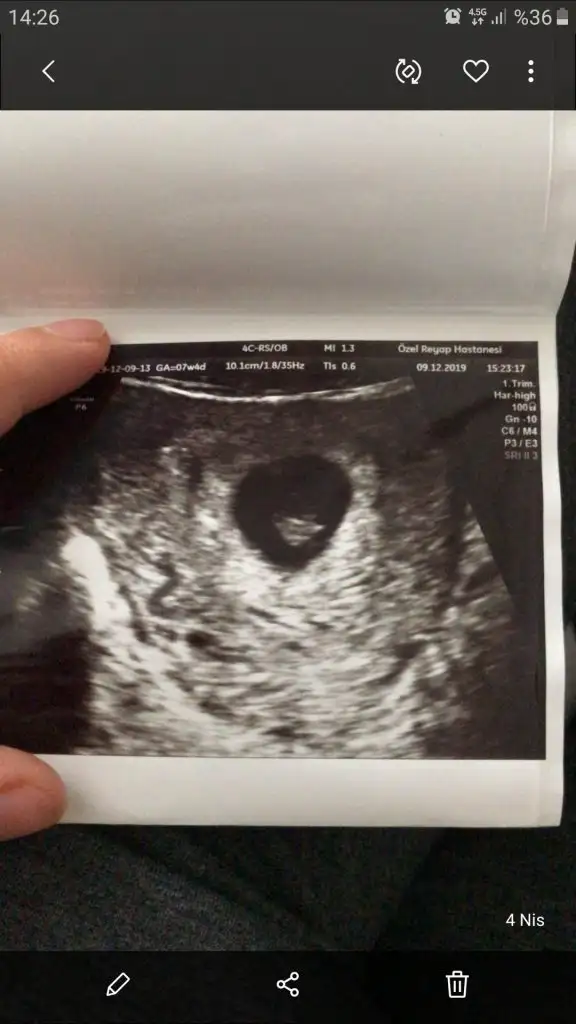

Merhaba bizim de 13. Hafta böyle sizce nedir :)Slm arkadaşlar nub teorisi konumuzda yaptıgım tahminleri ankete tıklayın yuzdesini görelim